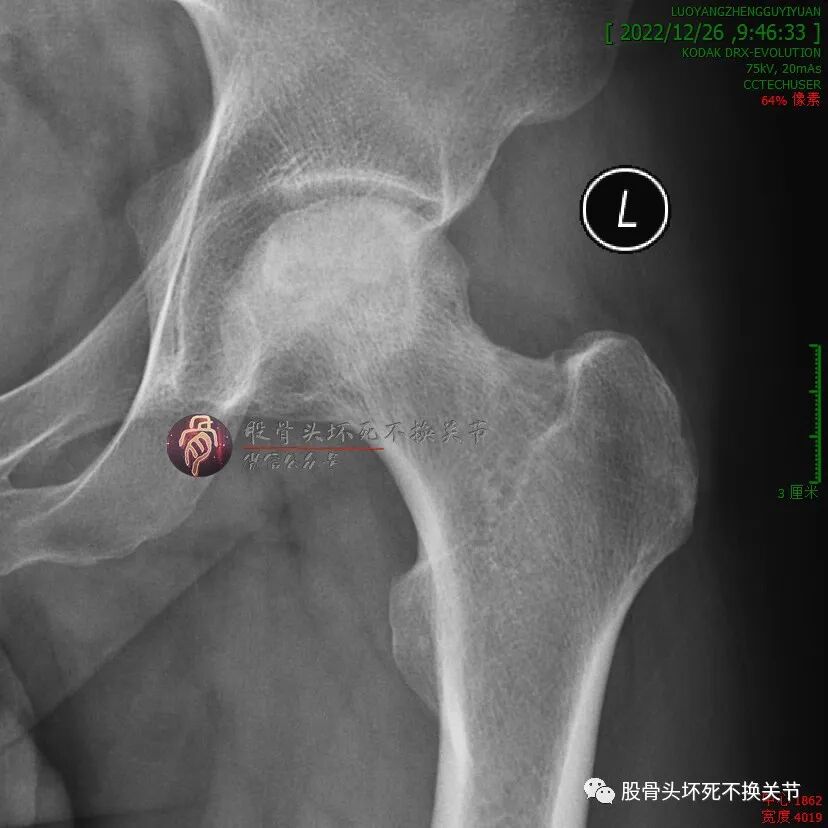

但是,疼痛缓解给予病人莫大希望,开始定期门诊治疗(不用住院、随治随走那种),半年后复查:

这次复查比初次就诊时明显好转,骨密度明显提高,疼痛基本全无,恢复一般的生活、工作能力。

继续定期门诊治疗,又过了5个月:

还行吧,骨密度就那样。